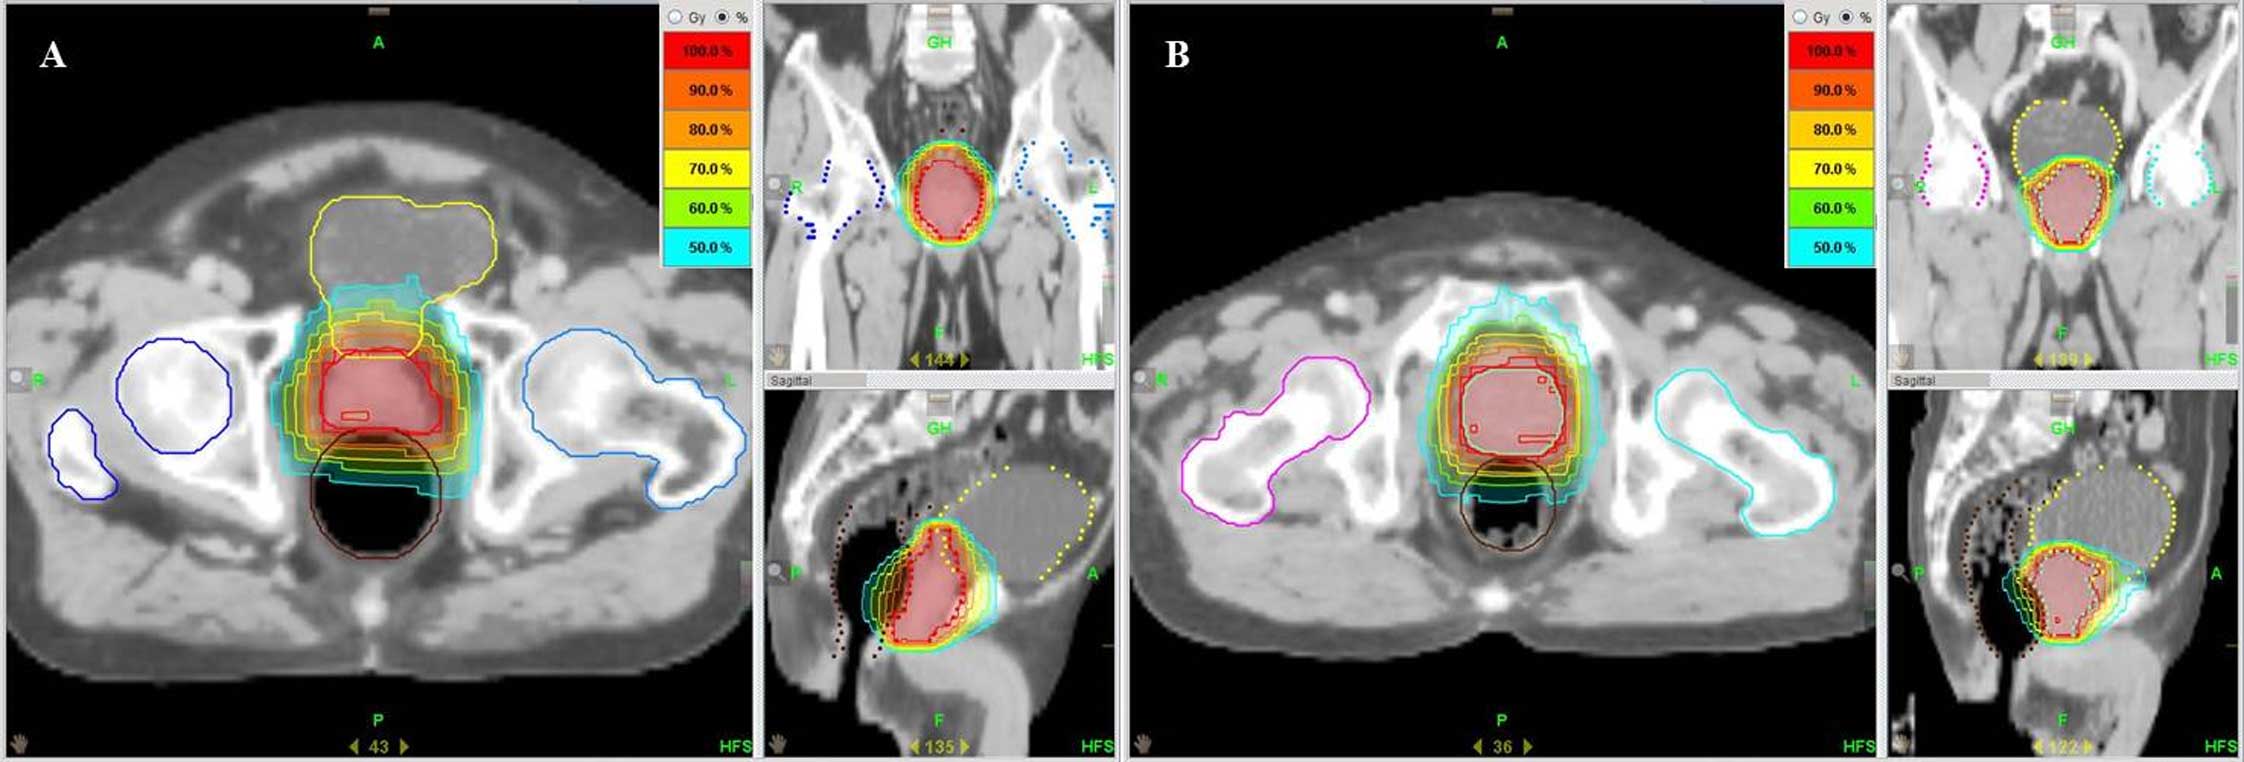

Salvage helical tomotherapy for prostate cancer recurrence following definitive external beam radiotherapy: A case report

Salvage prostatectomy for recurrent prostate cancer after external beam radiotherapy (EBRT) has resulted in positive outcomes; however, it is technically challenging and is associated with a number of risks. When a patient exhibits recurrent prostate cancer following definitive EBRT and presents with comorbidities meaning that they cannot receive a prostatectomy, it is difficult to treat due to the numerous limitations of current salvage therapies. In the present study, two cases of salvage reirradiation using helical tomotherapy for locally recurrent prostate cancer following definitive EBRT are presented. The two patients received EBRT without severe complications. Local recurrence was confirmed by serum levels of prostate‑specific antigen, repeat prostate biopsy, prostate magnetic resonance imaging and a bone scan. Salvage reirradiation using helical tomotherapy was performed and resulted in promising outcomes without any complications. In conclusion, helical tomotherapy can be a safe and effective salvage treatment modality for locally recurrent prostate cancer following definitive EBRT.

Figure 1